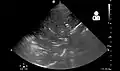

Lung ultrasound may also be useful in helping to make the diagnosis.[76] Ultrasound is radiation free and can be done at bedside. However, ultrasound requires specific skills to operate the machine and interpret the findings.[41] It may be more accurate than chest X-ray.[77]

-

Pneumonia seen by ultrasound[78]

Pneumonia seen by ultrasound[78] -